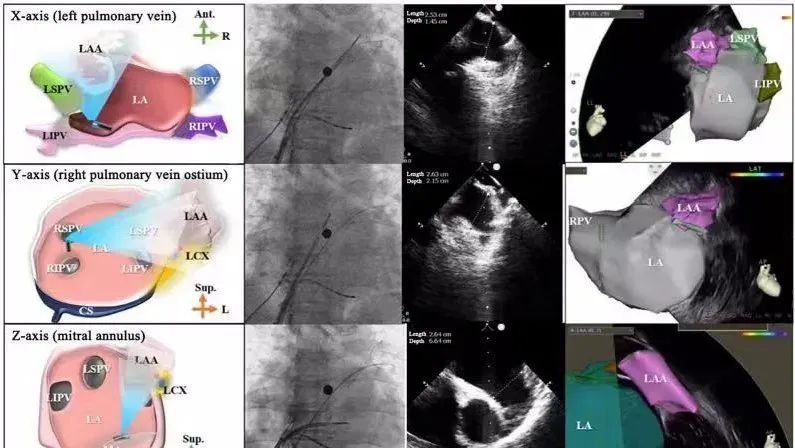

一種與心導管檢查相結合的超聲心動圖診斷新興技術,通過將超聲探頭置于心腔內部,發(fā)射并接收超聲信號,來精確獲取心臟解剖結構、心臟血流動力學等信息的實時成像。與其他影像技術相比,ICE技術具有操作簡單、無輻射、安全性高、手術效率高、實用等優(yōu)勢,ICE在很大程度上有望取代經食道超聲心動圖(TEE),成為電生理和結構性心臟病領域的理想成像方式。

心腔內超聲(ICE)技術壁壘極高,國內主要廠商核心部件仍舊為進口,集成了超聲和圖像處理最前端技術,包括超聲探頭、線纜、軟件成像算法等,是當前內窺超聲方向最具挑戰(zhàn)的領域。ICE的應用經歷了2D平面成像、3D三維立體成像、以及4D的實時三維立體成像階段。